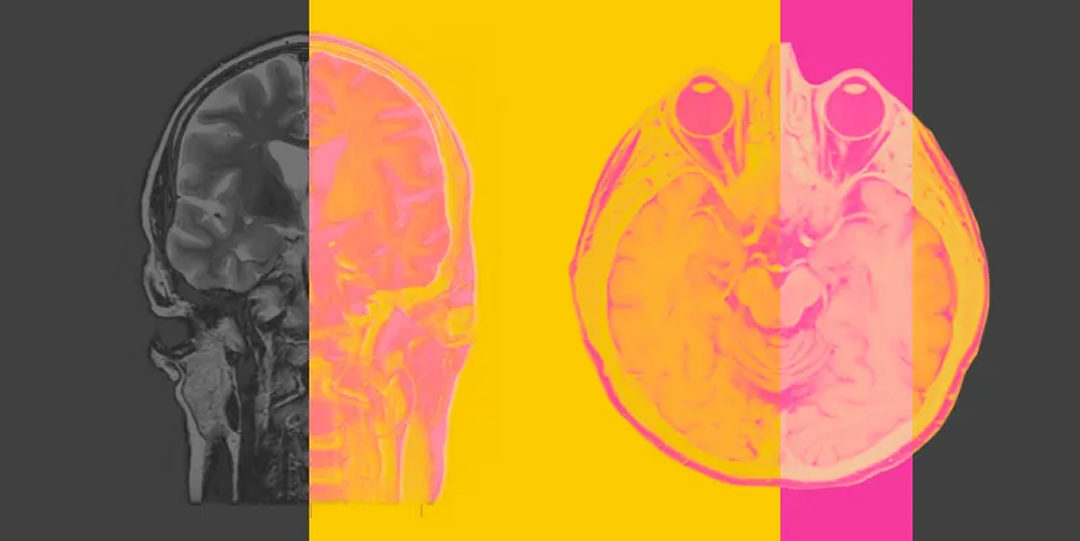

Мозговые центры обучения и памяти